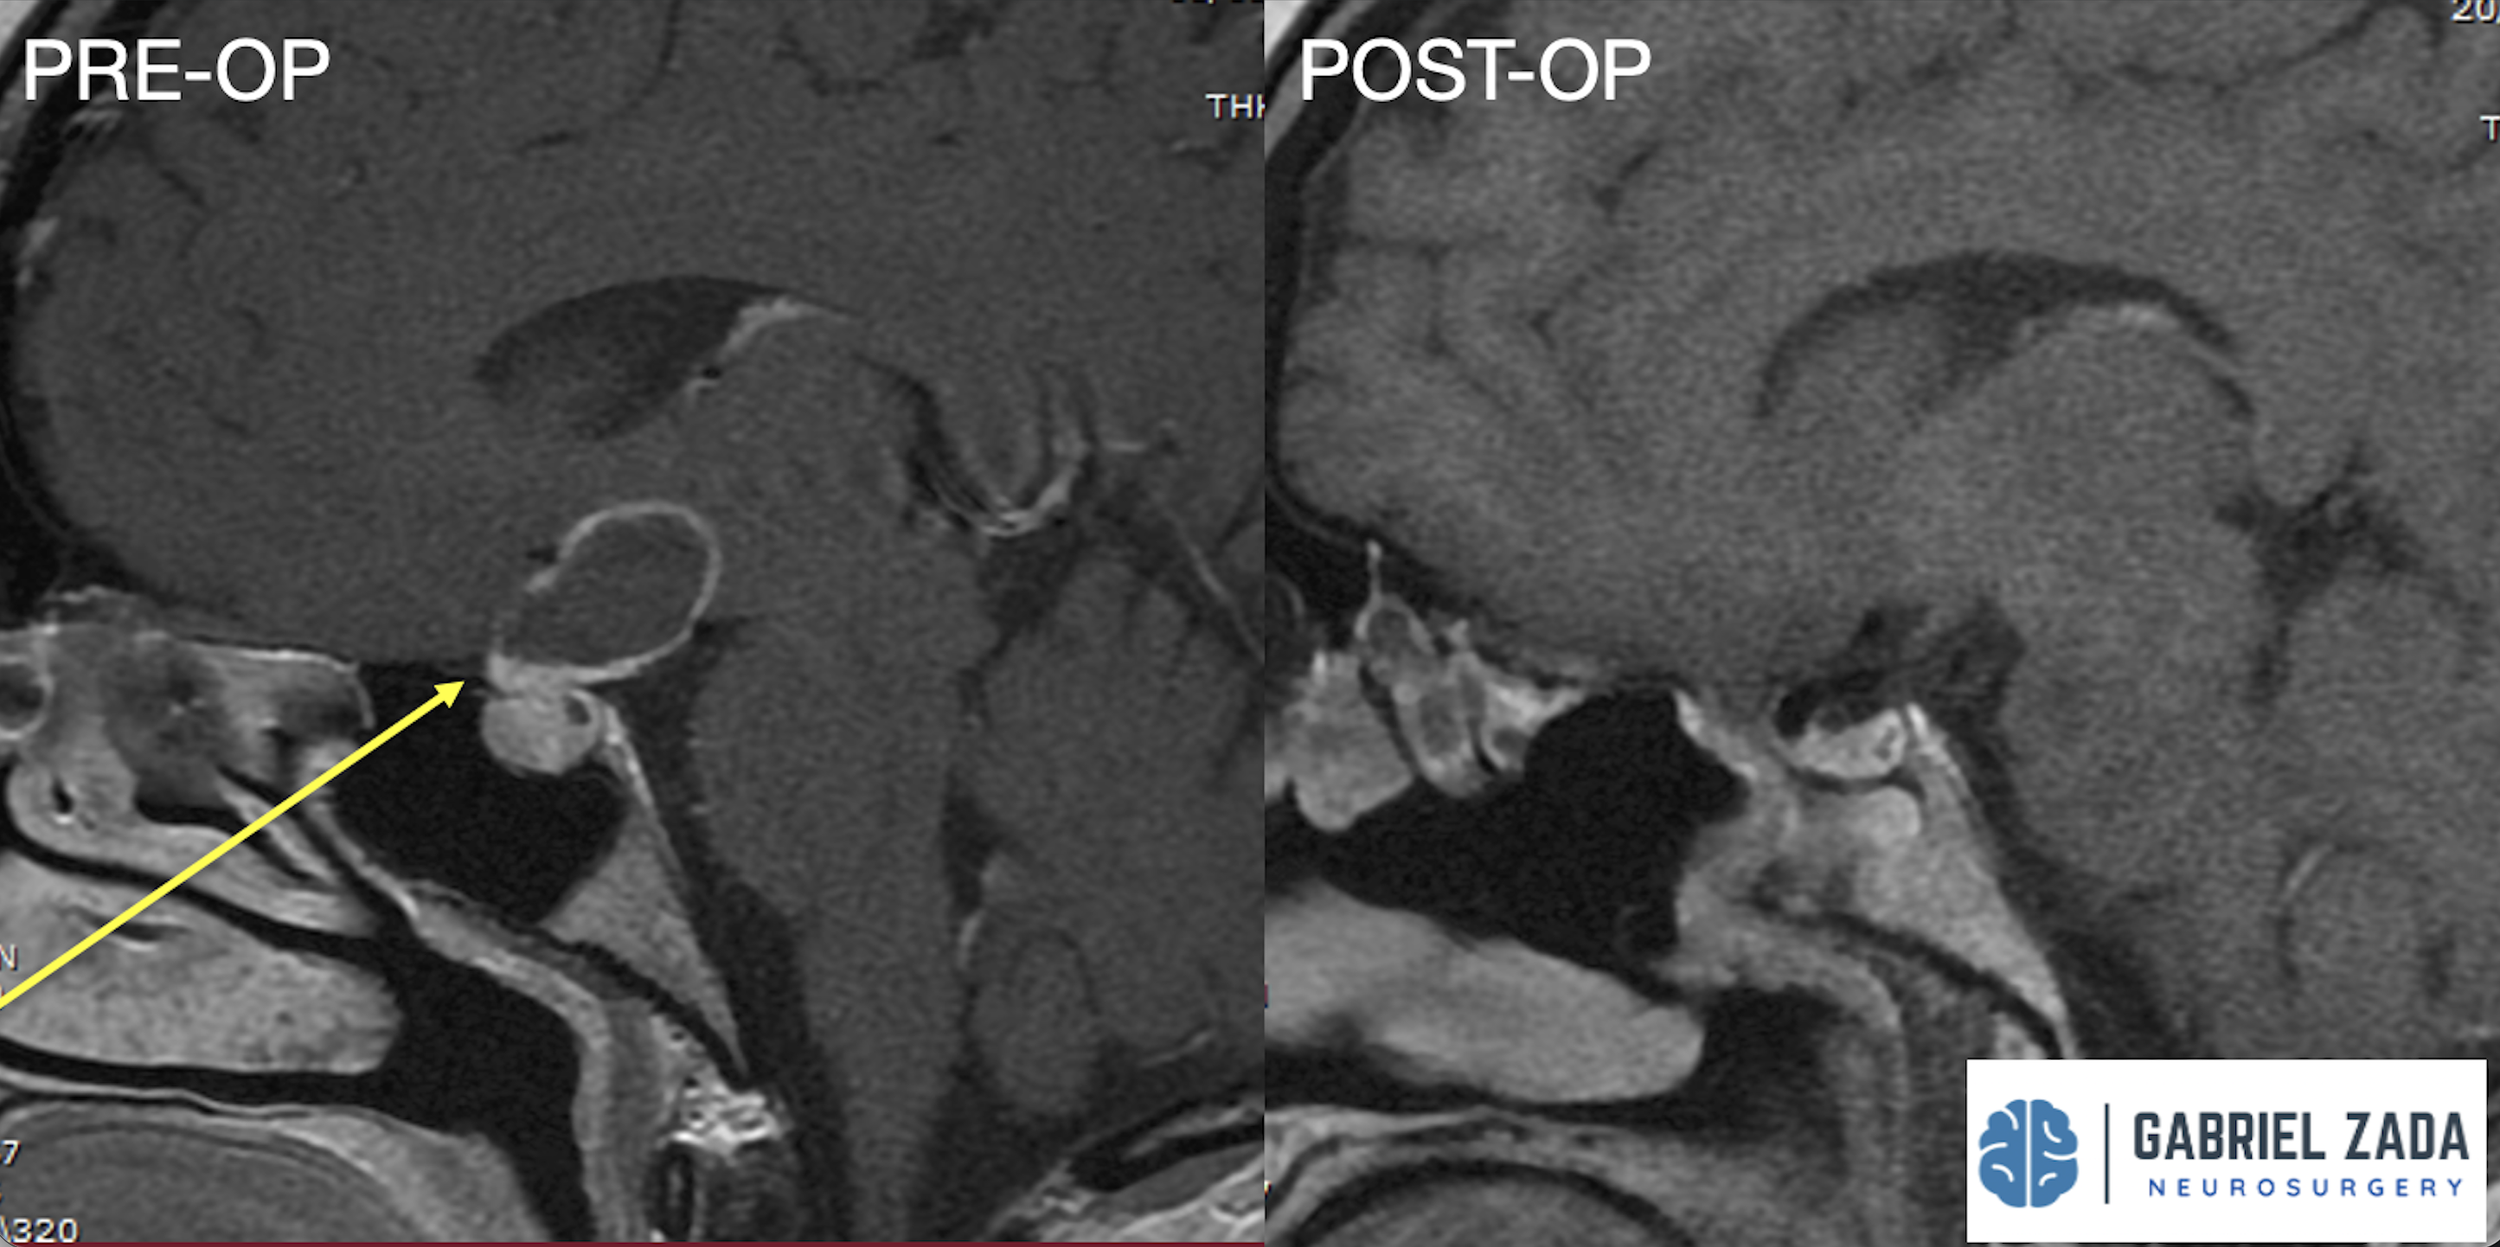

Explore this comprehensive gallery featuring pre‑ and post‑operative imaging of patients with skull‑base tumors treated by Gabriel Zada, MD, MS, FAANS, FACS. These cases highlight Dr. Zada’s expertise in advanced neurosurgical techniques and outcomes.

*Representative cases shown for educational purposes. All images de-identified. Individual results vary.